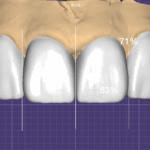

[사진 1 참조] 초진 시 기존 보철물 상태 — 불투명하고 어색한 라미네이트

[사진 2 참조] 단일 블록 크라운(좌) vs 다층 빌드업 크라운(우) — 투명도 비교

[사진 3 참조] 형태 디테일 비교 — 자연스러운 라미네이트 vs. 불투명하고 어색한 라미네이트